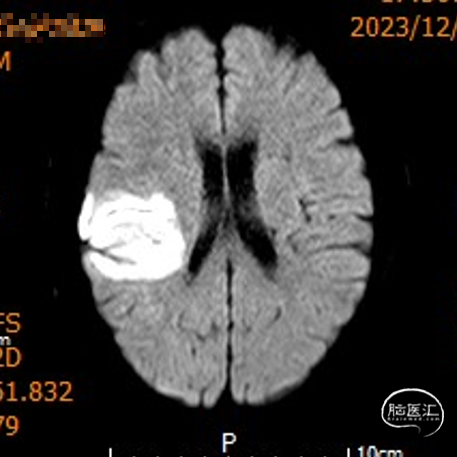

影像信息

颅脑CT示:

1.双侧侧脑室旁及右侧额顶叶多发脑梗死;

2.脑白质变性。

MRI示右侧颞顶叶及胼胝体急性脑梗死。